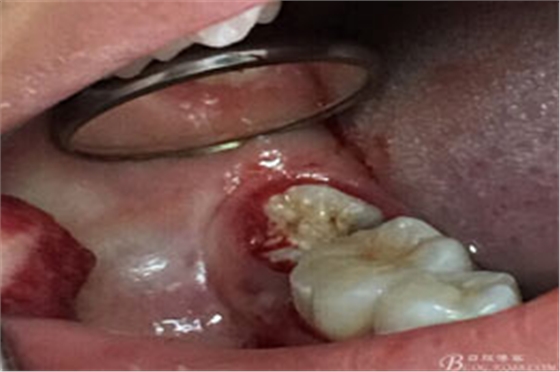

圖9.清理牙槽窩過后。多生牙的牙冠暴露在牙槽窩內(nèi)。

各種位置的埋伏牙常常會壓迫臨近牙齒的牙根吸收,導(dǎo)致鄰牙被拔除。多見于上頜埋伏尖牙壓迫中切牙牙根吸收、下頜埋伏智齒導(dǎo)致第二磨牙牙根吸收等等,所以提示我們口腔醫(yī)生要注意埋伏的診治。本病例是一例多生牙壓迫37牙根吸收,導(dǎo)致37被拔除,實屬少見。